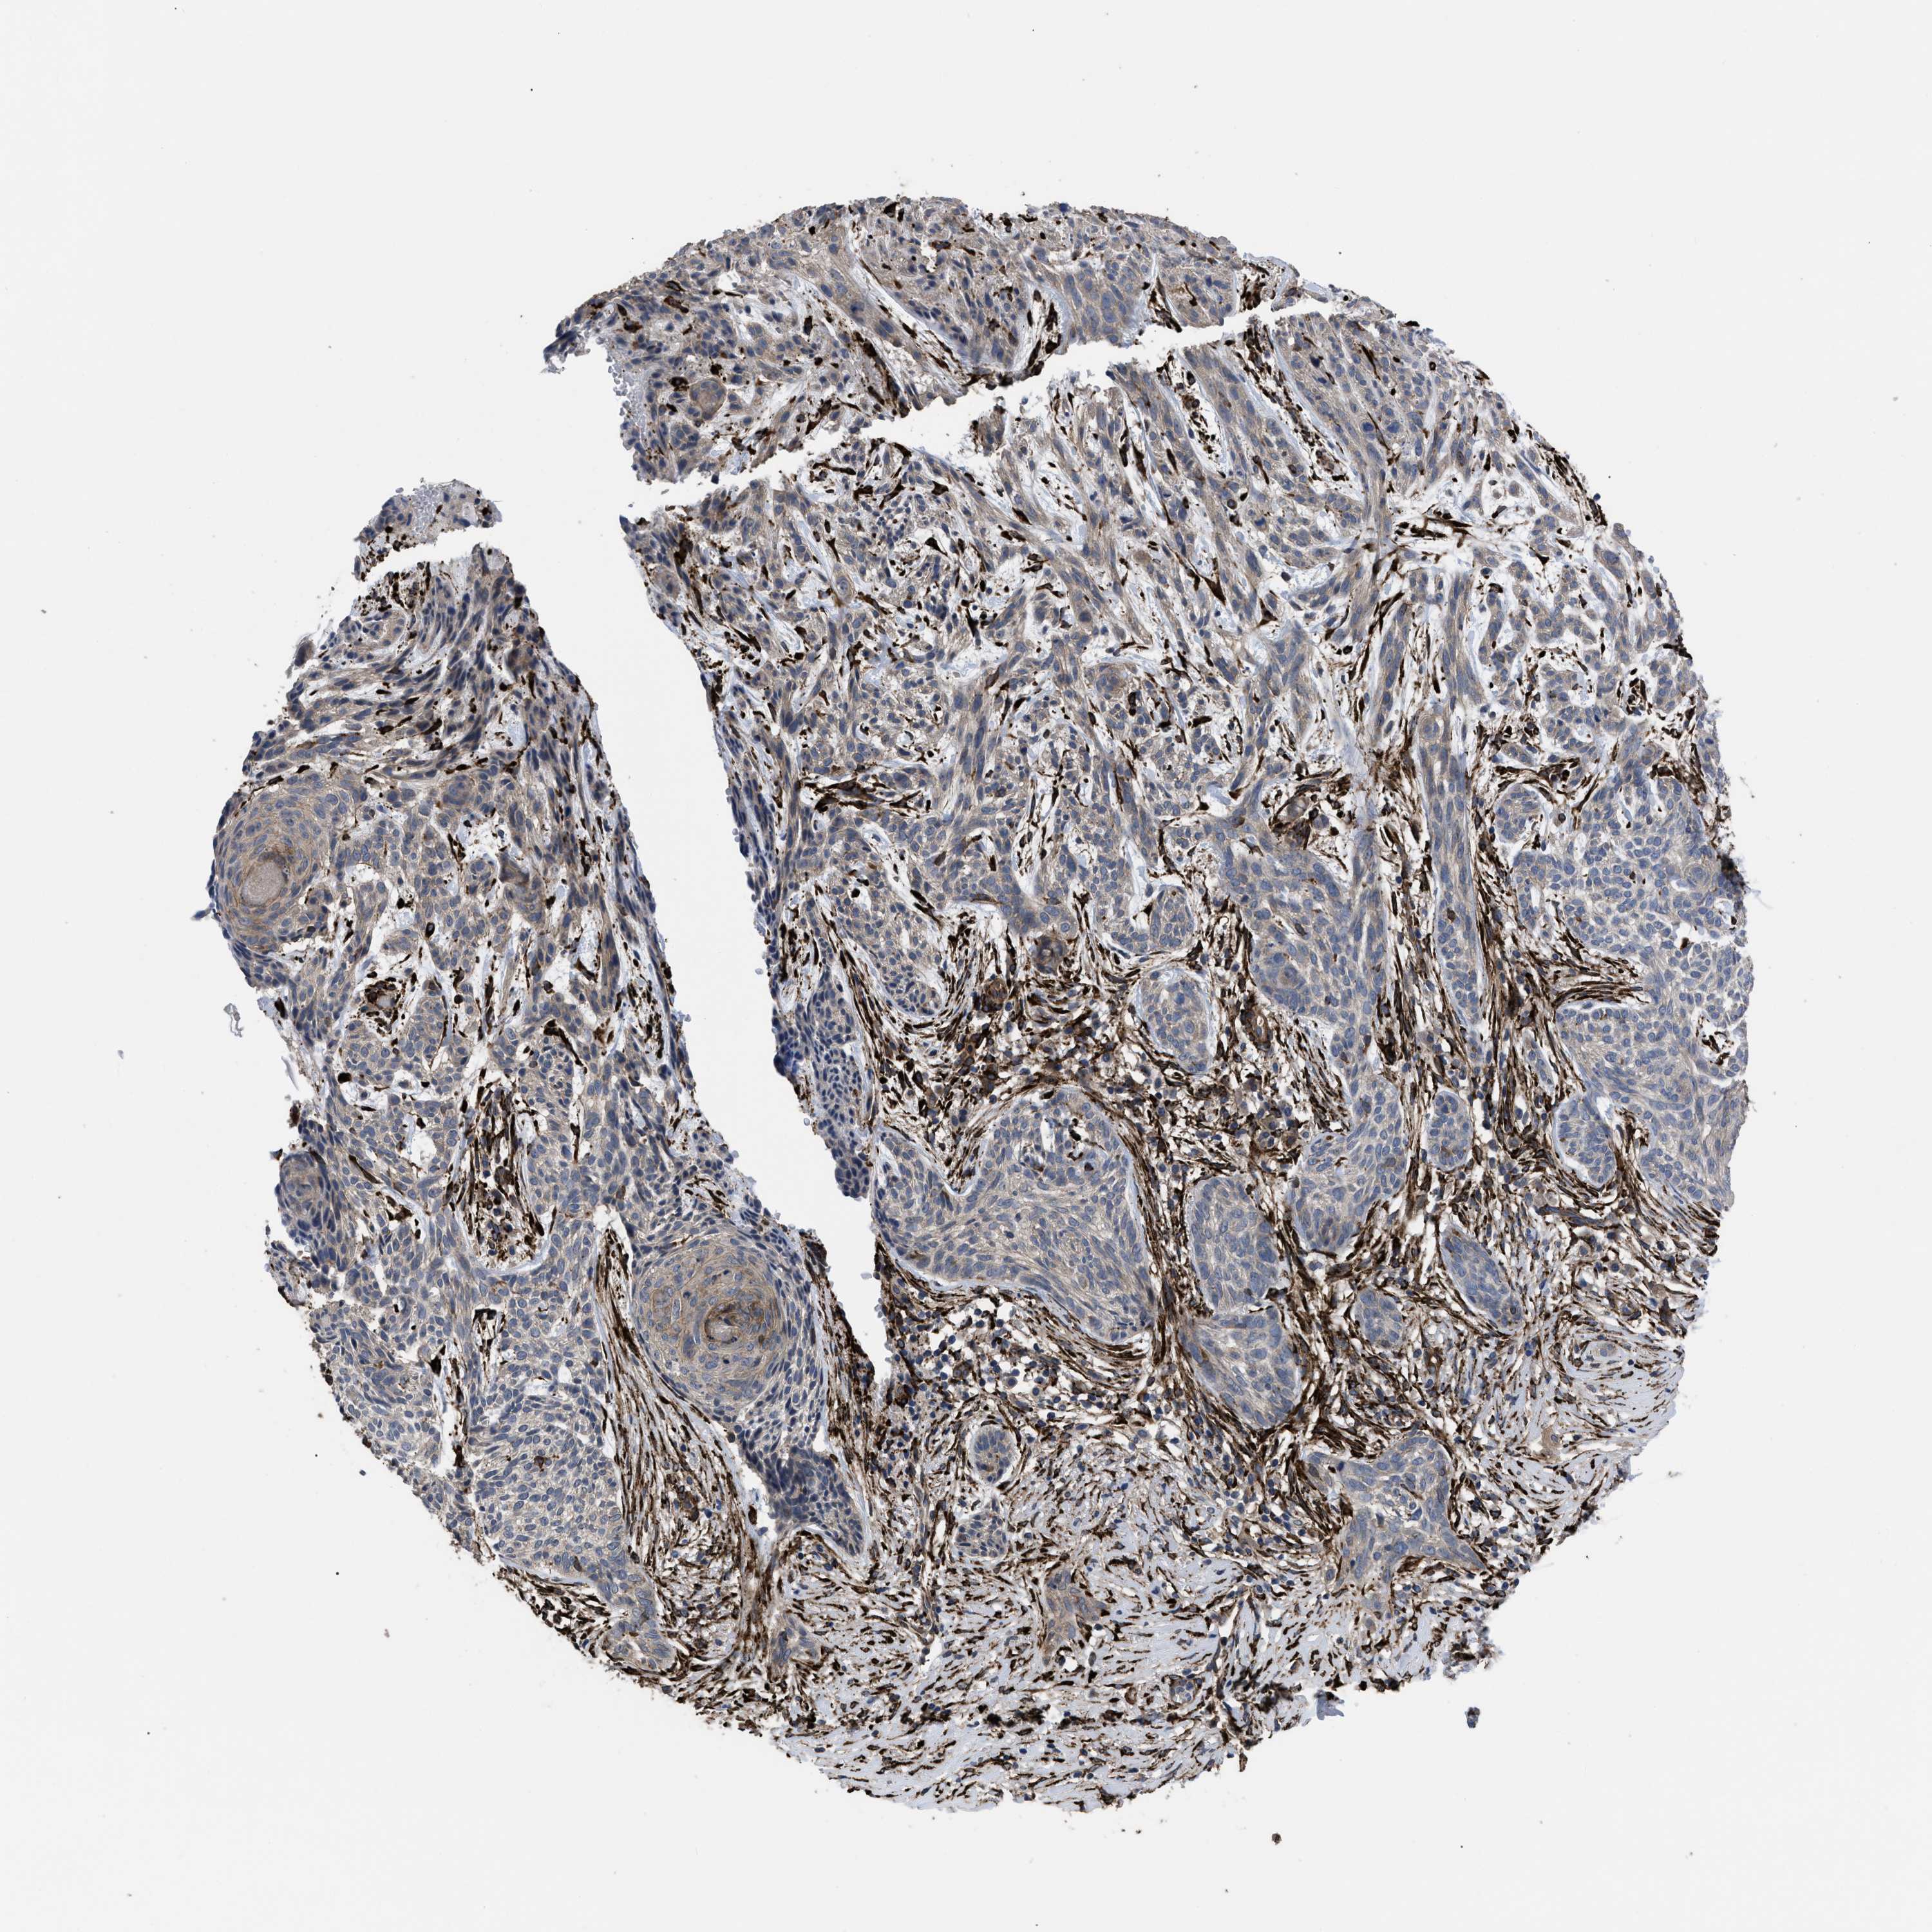

SKIN CANCER - Protein expressioni

A mouse-over function shows sample information and annotation data. Click on an image to view it in a full screen mode. Samples can be filtered based on level of antibody staining by selecting one or several of the following categories: high, medium, low and not detected. The assay and annotation is described here.

Antibody stainingi

Antibody staining in the annotated cell types in the current human tissue is reported as not detected, low, medium, or high, based on conventional immunohistochemistry profiling in selected tissues. This score is based on the combination of the staining intensity and fraction of stained cells.

Each image is clickable and will lead to virtual microscopy that enables deeper exploration of all samples and also displays staining intensity scores, fraction scores and subcellular localization as well as patient and tissue information for each sample.

Antibody HPA018038

Antibody HPA020762

Staining

High

Medium

Low

Not detected

Intensity

Strong

Moderate

Weak

Negative

Quantity

>75%

75%-25%

<25%

None

Location

Nuclear

Cytoplasmic/membranous

Cytoplasmic/membranous,nuclear

Squamous cell carcinoma in situ, NOS

Squamous cell carcinoma, NOS

Squamous cell carcinoma, metastatic, NOS

Basal cell carcinoma